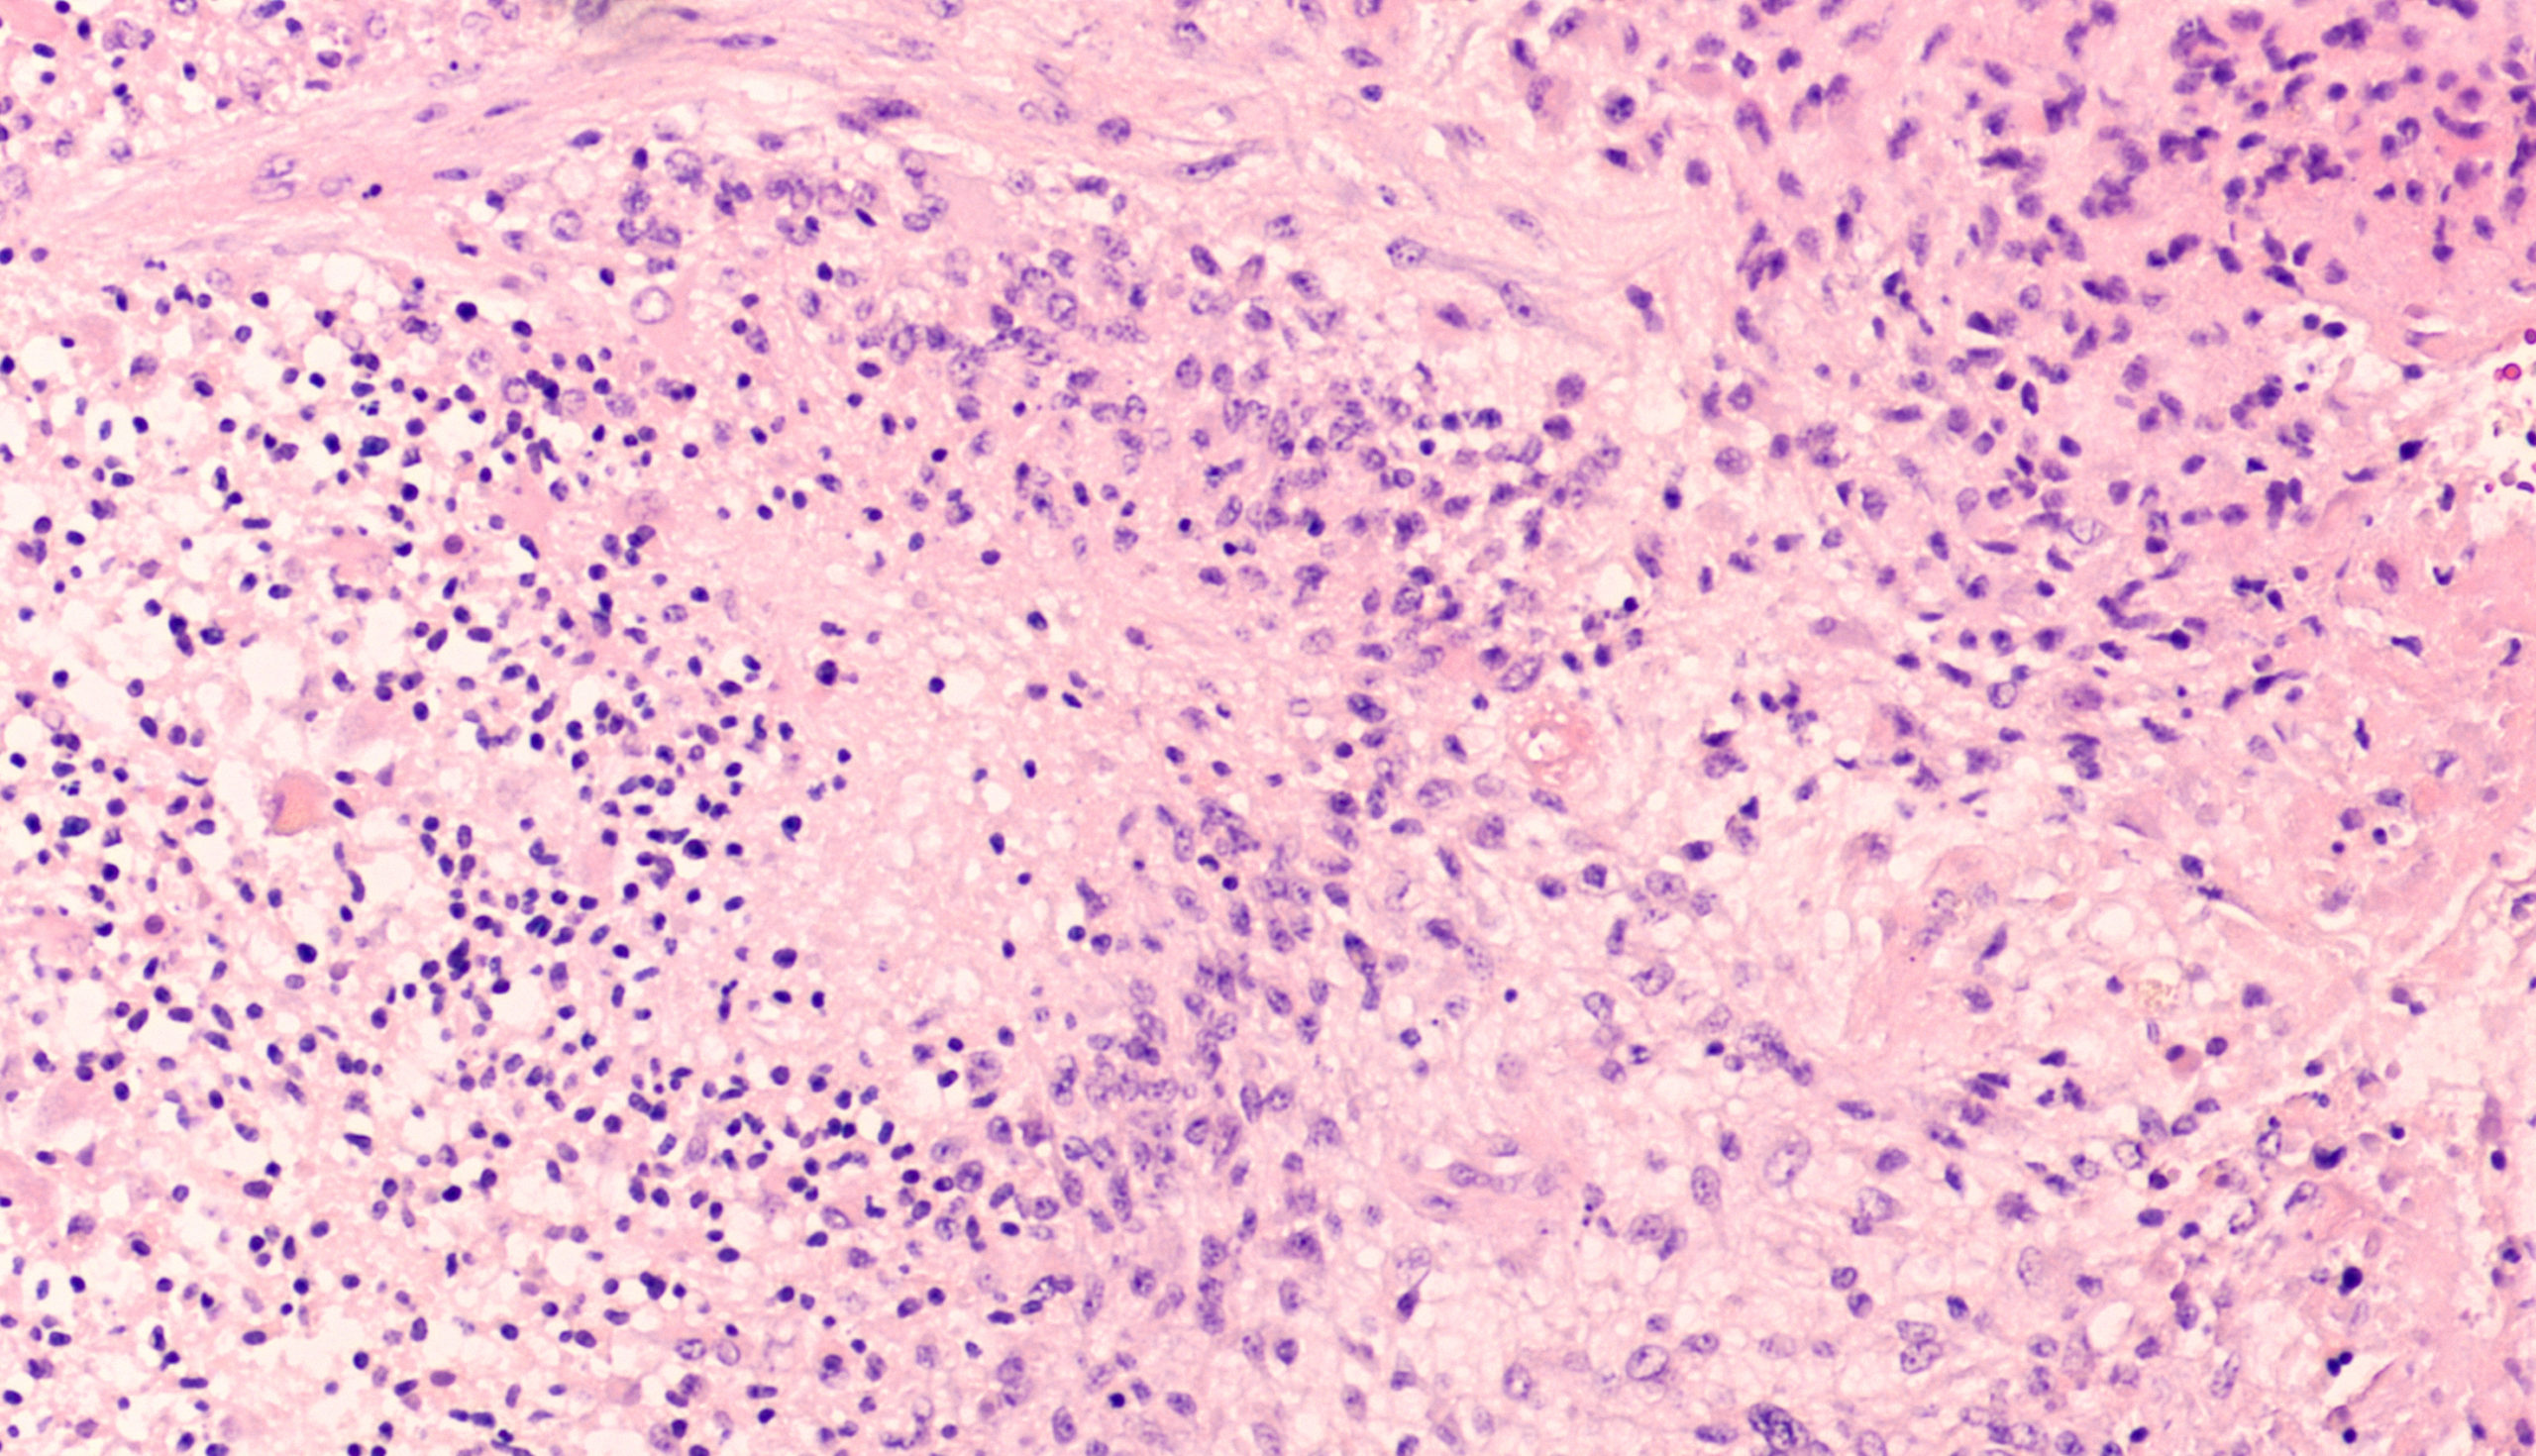

Tumor cells with extensive necrosis (H&E, X200). Download Scientific Malignant Tumor Necrosis Here, we investigated gene expression patterns. Cells possess sensing mechanisms to detect damage, malfunction and fitness disparities. Tumor necrosis has been found to be associated with tumorigenesis and poor prognosis for years, 1 but the role of necrosis in tumor. We aimed at inquiring whether accelerated necrosis, often the result of prolonged anticancer treatment can, by itself, contribute to tumor. Malignant Tumor Necrosis.